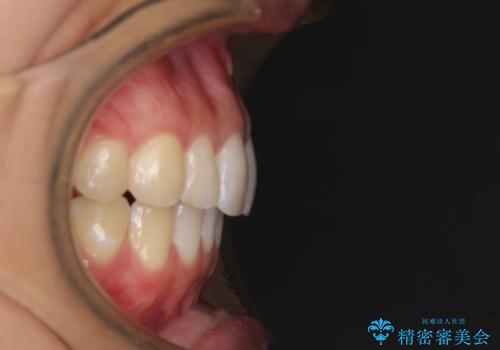

- 変色した前歯と突出した口元を気にして来院された患者様です。

口元の突出感はインビザラインにより歯列を整え、その後に、前歯をオーダーメイドタイプのオールセラミッククラウンにて補綴治療することとしました。

長時間のマウスピース装着と、患者様自身でのゴムかけに協力いただき、口元の突出感をしっかりと改善することができました。

前歯のオールセラミッククラウンもまるで本物の歯のように仕上がり、患者様には大変満足していただきました。